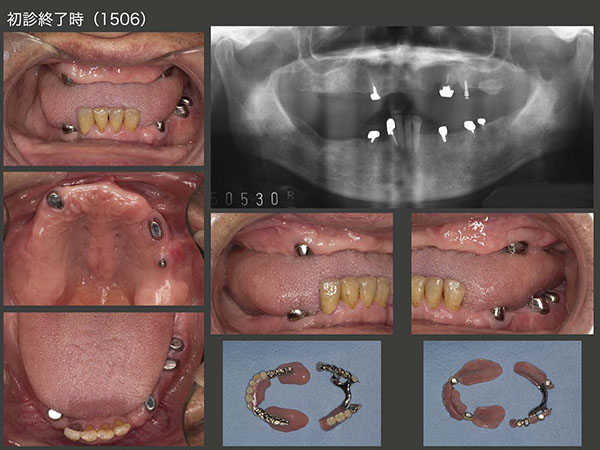

暫間義歯で下顎位の確保を行い,次の段階の治療に進んだ.まず,残根状態の右上5を矯正的挺出することで抜きやすくしたうえで抜去し,左上5部に移植した.なお遠心にミニインプラントを植立し,移植歯の固定を図った.つぎに,右上6の口蓋根を抜去し,右下4部に移植した.なお,頰側根は廃棄した.移植が成功すれば,上下顎とも切歯を除いた左右両側に支台歯が存在することになり,義歯の安定性が向上する.

右上5,6を抜歯したことで顎堤が吸収したが,それでもまだ義歯を製作するだけのスペースが得られなかった.そこで2013年3月,顎堤自体の歯槽骨を削去し,強制的に義歯製作のためのスペースを確保した.

上段は2013年6月の状態.右上3,右下4(移植歯)および左下4に暫間のOPAアタッチメントを装着した.なお,左上のミニインプラントにもOリングゴムを装着してOPAアタッチメントの代役とした.

2015年6月,初診終了時の状態.初診より3年2ヵ月が経過してしまった.患者さんには長い間通院してくださり,心より感謝する次第である.上下顎とも支台歯が左右側にあることから,義歯の安定はすこぶるよい.左上のミニインプラントは役目が終わったので本来なら除去すべきところであるが,特に問題もないことからこのまま置いておくことにした.